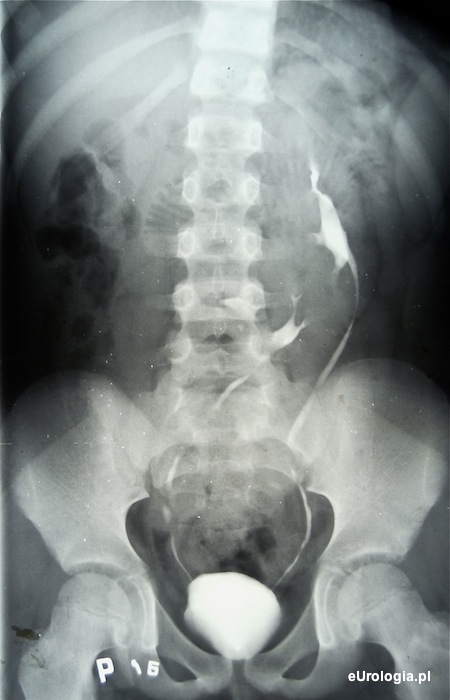

Fot. Ektopia skrzyżowana nerki prawej.

Skrzyżowana ektopia nerki jest rzadką wadą rozwojową polegającą na przemieszczeniu nerki na stronę przeciwną, przy czym moczowód nerki ektopicznej przecina linię pośrodkową ciała i uchodzi do pęcherza moczowego w miejscu typowym.

Częstość występowania przemieszczenia skrzyżowanego nerki szacuje się na 0,05 do 0,1 %. Najczęstszą postacią wady jest wariant ze zrośnięciem biegunów - ok. 90 % wszystkich przypadków.